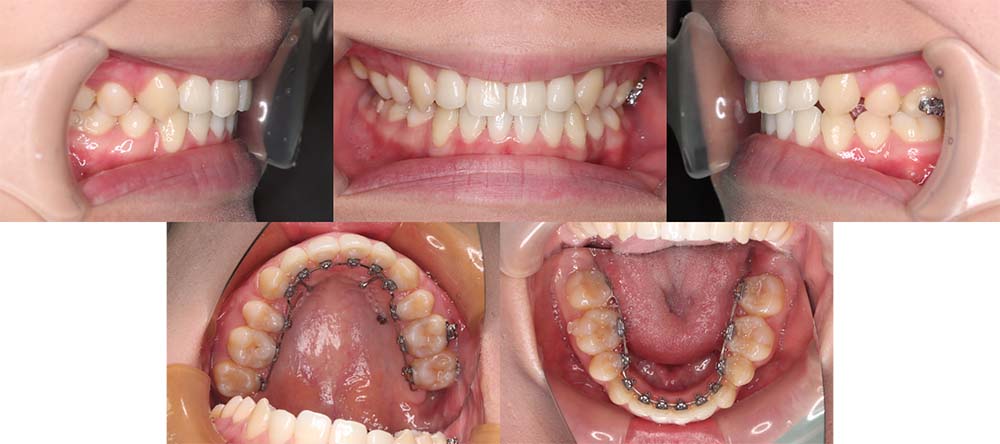

| 症例分類 | 上顎前突、叢生 |

| 診断名 | 上下叢生を伴う骨格性および歯性上顎前突 |

| 主訴 | 歯並びが悪いのが気になる、口元が気になる |

| 年齢 | 19歳5ヶ月 |

| 性別 | 女性 |

| 抜歯部位 | 上の左右第一小臼歯(2本) |

| 使用装置 | 上下裏側のワイヤー装置 |

| 治療期間 | 2年5ヶ月 |

| 保定装置 | 固定式保定装置、取り外し式保定装置(8時間) |

| 費用 |

[検査・診断料] ¥49,500 [基本施術料] ¥1,331,000 [調整料] ¥5,500/回 [抜歯] ¥5,500/本 [保定装置] ¥55,000(税込) 抜歯や虫歯治療は他院にて費用が別途かかります。(抜歯¥4,000〜10,000/本)

上顎前突で上の歯がかなり前にきているため、上顎両側第一小臼歯を抜去して治療を行いました。上の前歯をしっかりと舌側に移動しないといけないため、矯正用アンカースクリューを使用しました。また、下顎はわずかに歯の間の削合(ディスキング)を行い、初診時より歯が前方に出ないように治療を進めました。

口唇閉鎖不全もありましたが、上の前歯が舌側に移動することにより改善することができ、問題なく咬合させることができました。